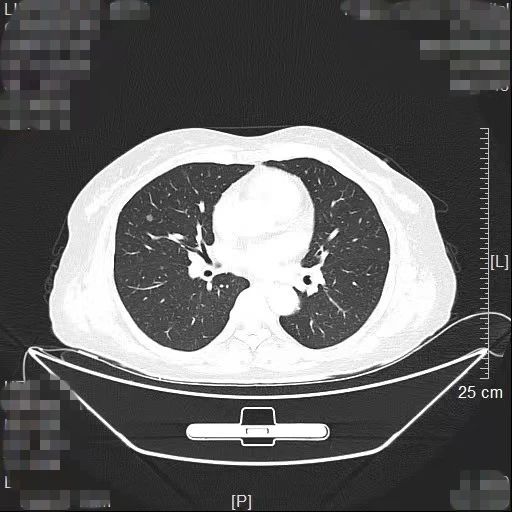

患者林女士今年65岁,长期旅居国外的她在回国后常规体检时查出右肺有2个高危的磨玻璃结节,慕名找到我院胸部肿瘤外科方卫民主任医师。医生团队详细分析了患者的肺部CT及三维重建结果,发现2个结节分别位于右上肺后段边缘及右中肺叶中央,如果直接采用手术切除的方法,要多切除整个右肺中叶,将损失较多的正常肺组织,影响生活质量,得不偿失。

三维重建结果